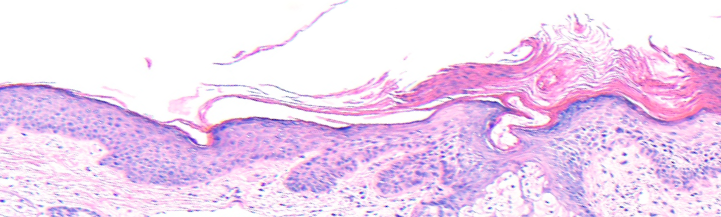

VA183: Right Cheek, Actinic Keratosis, Hypertrophic, Ulcerated

- Arrows indicate base of epidermal thickening